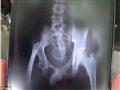

بدأ "أكمل" يعاني هذه الحالة في عام 2016، وتأتي على شكل نوبات من الألم، ما اضطر الصبي للذهاب إلى المستشفى عدة مرات، وقد وضع مؤخرًا بيضتين دفعة واحدة على مرأى الأطباء الذين وصفوا حالته بأنها معجزة، وفقًا لموقع صحيفة "ديلي ميل" البريطانية.

ويقول الأطباء إنه من المستحيل أن يتشكل البيض داخل جسم الإنسان، وشكك متحدث باسم المستشفى فيما يحدث، وقال إن الصبي ربما يُدخل البيض عمداً إلى جسمه.